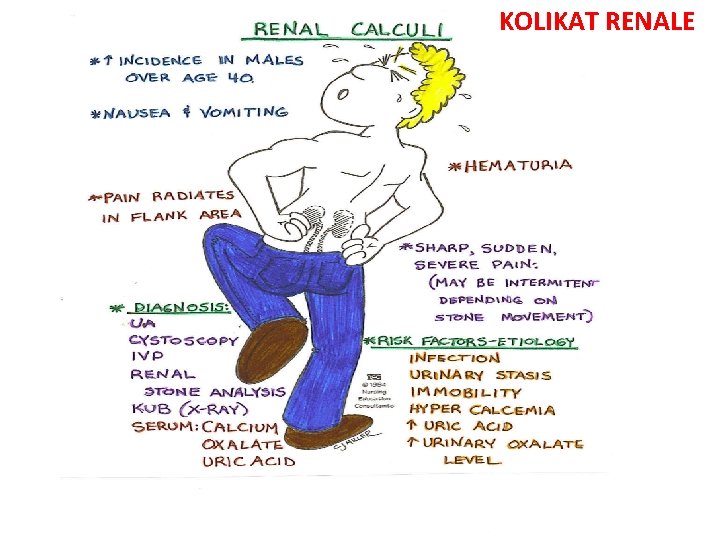

KOLIKAT RENALE

• Cdo femer ne moshen e fertilitetit qe paraqitet ne urgjence me dhimbje te abdomenit te poshtem duhet te beje TESTIN E SHTATZANISE!!!!!!!